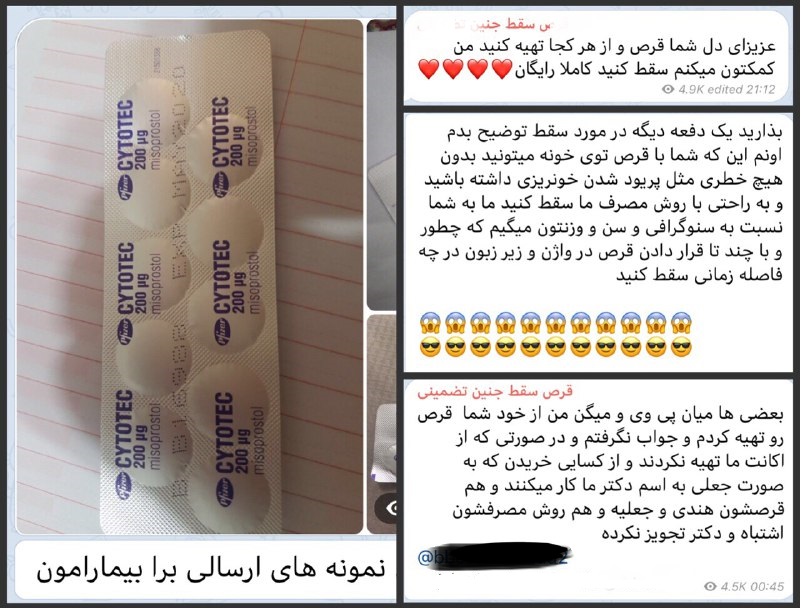

استفادههای مخرب از فضای مجازی به تبلیغات ختم نمیشود و به تازگی شاهد ارائه آموزشهایی هستیم که به یقین اثرات مخرب فردی و اجتماعی آن غیر قابل تصور خواهد بود؛ در کنار صفحات فروش و آموزش استفاده از مواد مخدر حالا کم کم سر و کله صفحات فروش قرص و آموزش سقط جنین پیدا شده است؛ ارائه آموزشهای نامناسب پزشکی به طور قطع به اندازه آموزش ساخت دینامیت در منزل یا آموزش کاشت و پرورش ماریجوانا در گلدانهای زینتی خطرناک خواهد بود.

ابتدای کار فقط حرف از تبلیغات در میان بود که با انجام تخلف برای پزشک و خطر برای بیمار همراه است، اما حالا شاهد آموزش این مسائل هستیم، زمانی که حرف از آموزش میزنیم به معنای بارها و بارها تکرار این اشتباه است، به معنای خطری است که نفر به نفر بین مردم این کشور پخش میشود؛ این آموزشها بدون شک هزاران بار خطرناکتر از تبلیغات است؛ در شرایطی که یکی از بزرگترین افتخارات جامعه پزشکی کشورمان رفع مشکل باروری و بچه دار شدن افراد بیمار است؛ مال دوستی برخی از افراد پزشک نما ممکن است حسرت تولد نوزادی را بر دل چند نفر باقی بگذارد.

, استفادههای مخرب از فضای مجازی به تبلیغات ختم نمیشود و به تازگی شاهد ارائه آموزشهایی هستیم که به یقین اثرات مخرب فردی و اجتماعی آن غیر قابل تصور خواهد بود؛ در کنار صفحات فروش و آموزش استفاده از مواد مخدر حالا کم کم سر و کله صفحات فروش قرص و آموزش سقط جنین پیدا شده است؛ ارائه آموزشهای نامناسب پزشکی به طور قطع به اندازه آموزش ساخت دینامیت در منزل یا آموزش کاشت و پرورش ماریجوانا در گلدانهای زینتی خطرناک خواهد بود.

,ابتدای کار فقط حرف از تبلیغات در میان بود که با انجام تخلف برای پزشک و خطر برای بیمار همراه است، اما حالا شاهد آموزش این مسائل هستیم، زمانی که حرف از آموزش میزنیم به معنای بارها و بارها تکرار این اشتباه است، به معنای خطری است که نفر به نفر بین مردم این کشور پخش میشود؛ این آموزشها بدون شک هزاران بار خطرناکتر از تبلیغات است؛ در شرایطی که یکی از بزرگترین افتخارات جامعه پزشکی کشورمان رفع مشکل باروری و بچه دار شدن افراد بیمار است؛ مال دوستی برخی از افراد پزشک نما ممکن است حسرت تولد نوزادی را بر دل چند نفر باقی بگذارد.